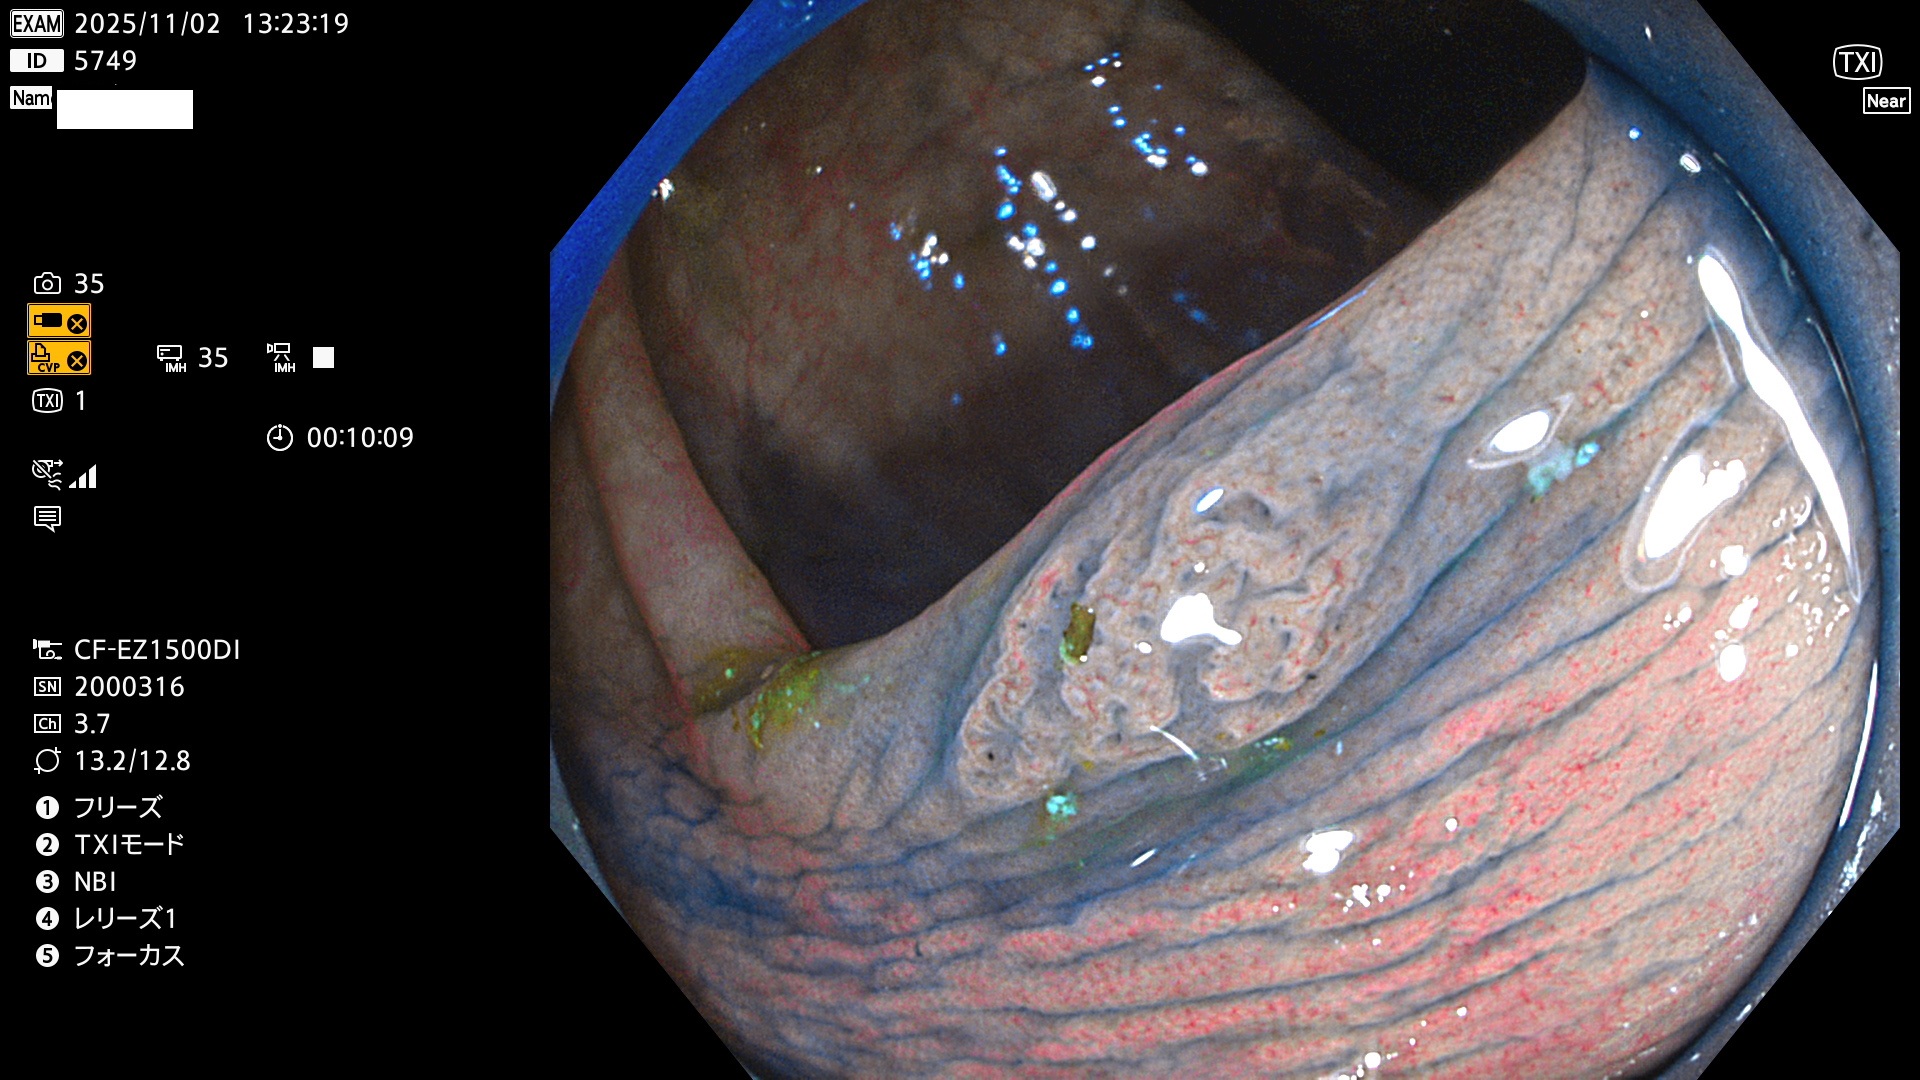

完全に平坦な物をUb、陥凹している物をUcと呼びます。Ubは認識が困難で、Ucはびらん(炎症)と紛らわしいために見落とされやすく、「内視鏡後・大腸癌」の原因になります。

毎週の検査(木・金・土・日)に発見されたUbとUc型・腺腫を、その週の日曜の夜にUPし1週間、提示します。

2025年10月30日〜11月2日の4日間(40件)9個 (Uc_ADR=9個/40人=23%)